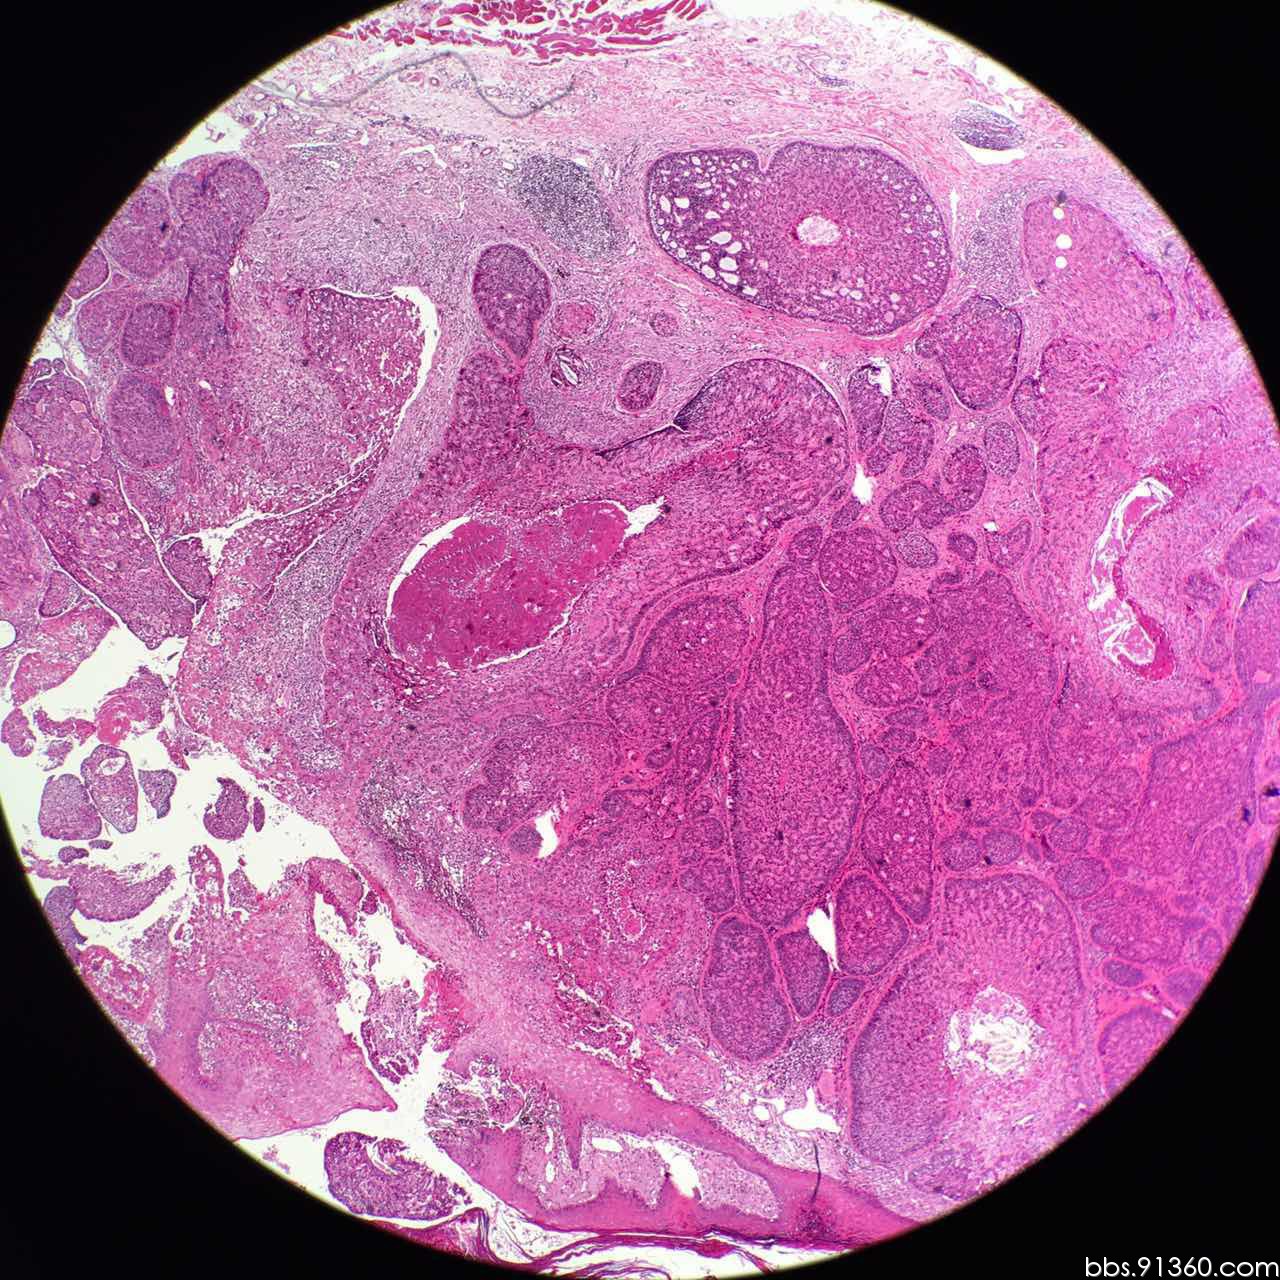

毛母细胞瘤恶变病例2016.05.04【91360皮肤沙龙案例37】

图片尺寸1280x1280